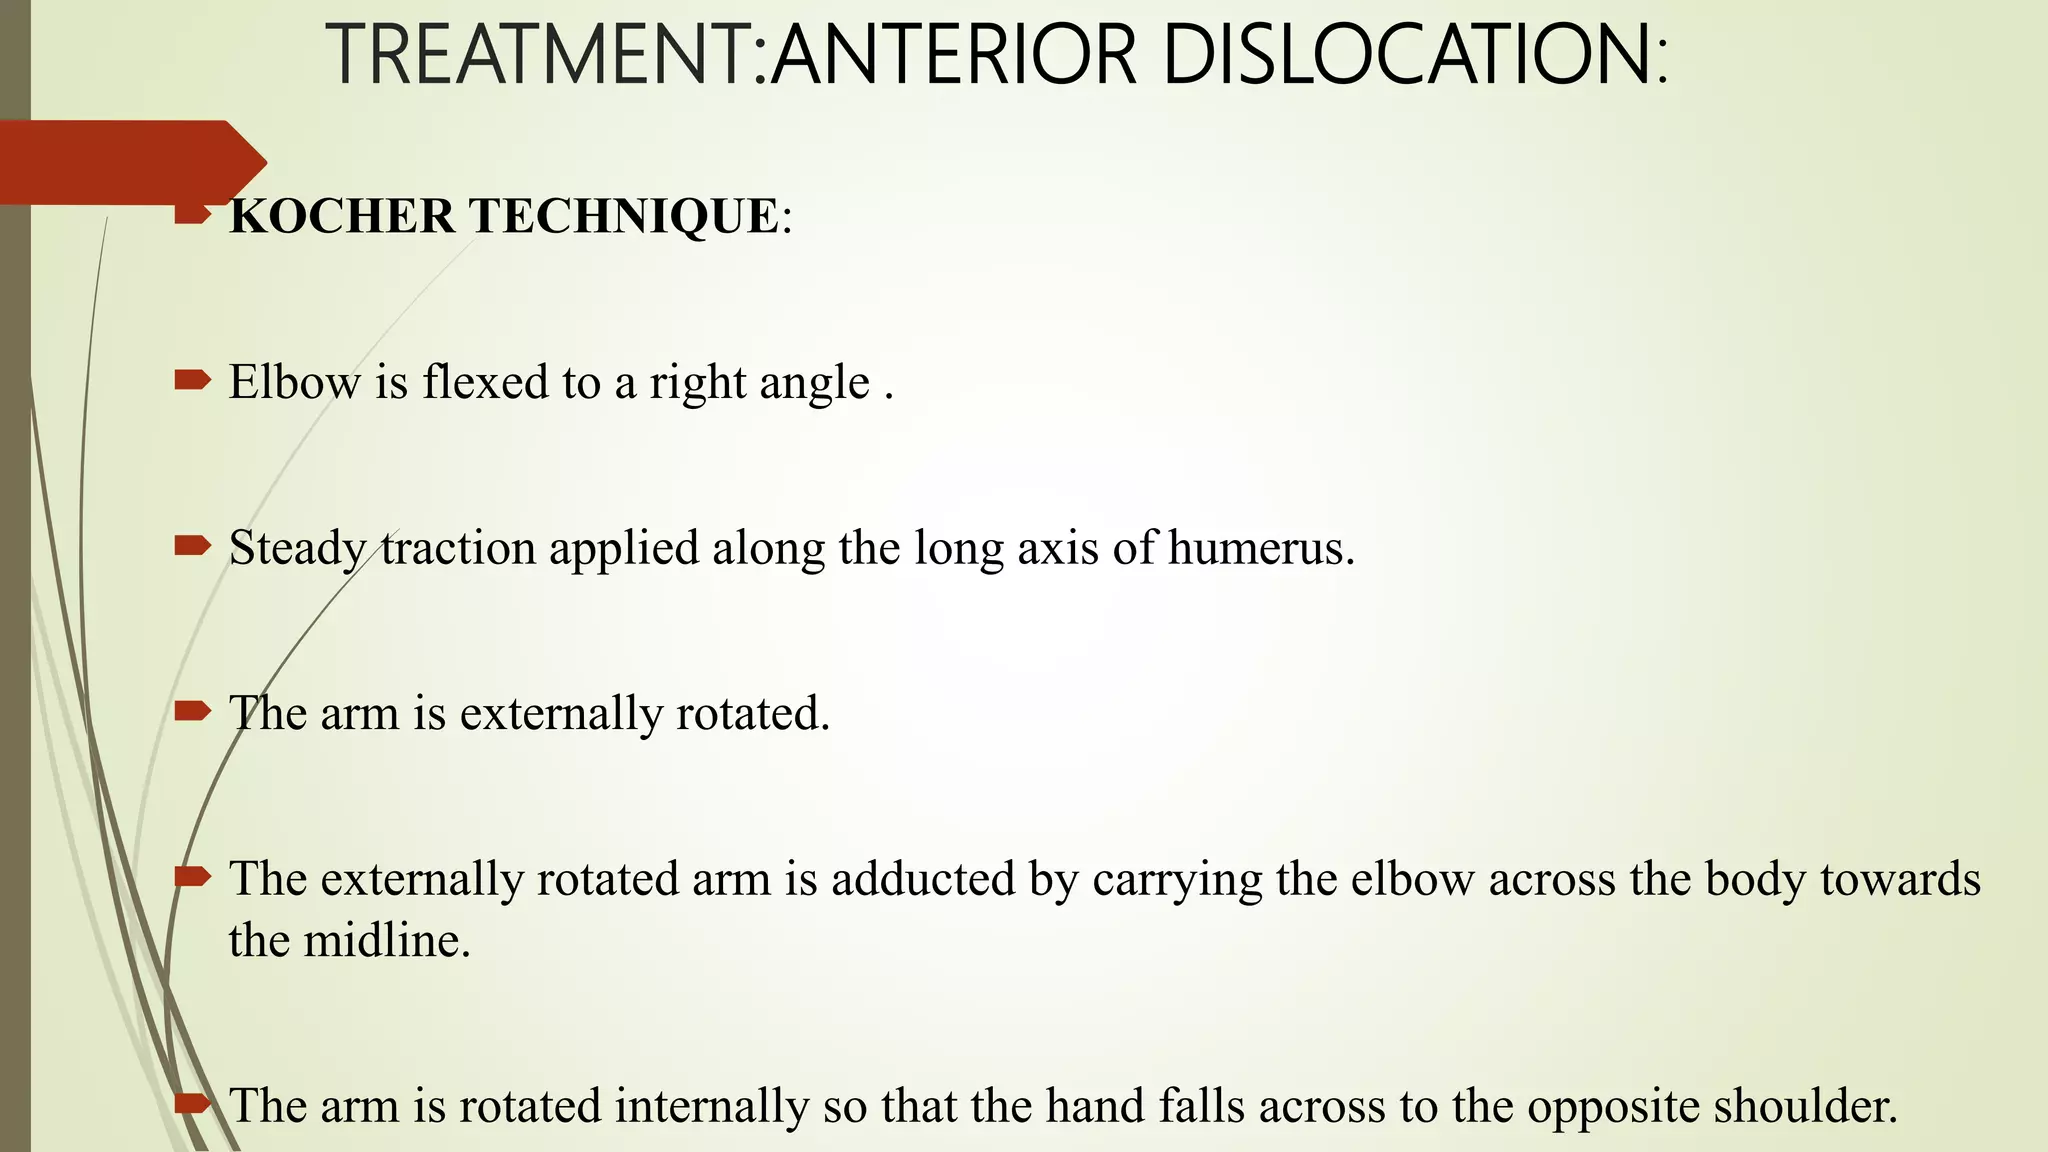

- Treatment involves closed reduction for most acute dislocations. Recurrent or complicated dislocations may require surgery and immobilization followed by physical therapy.